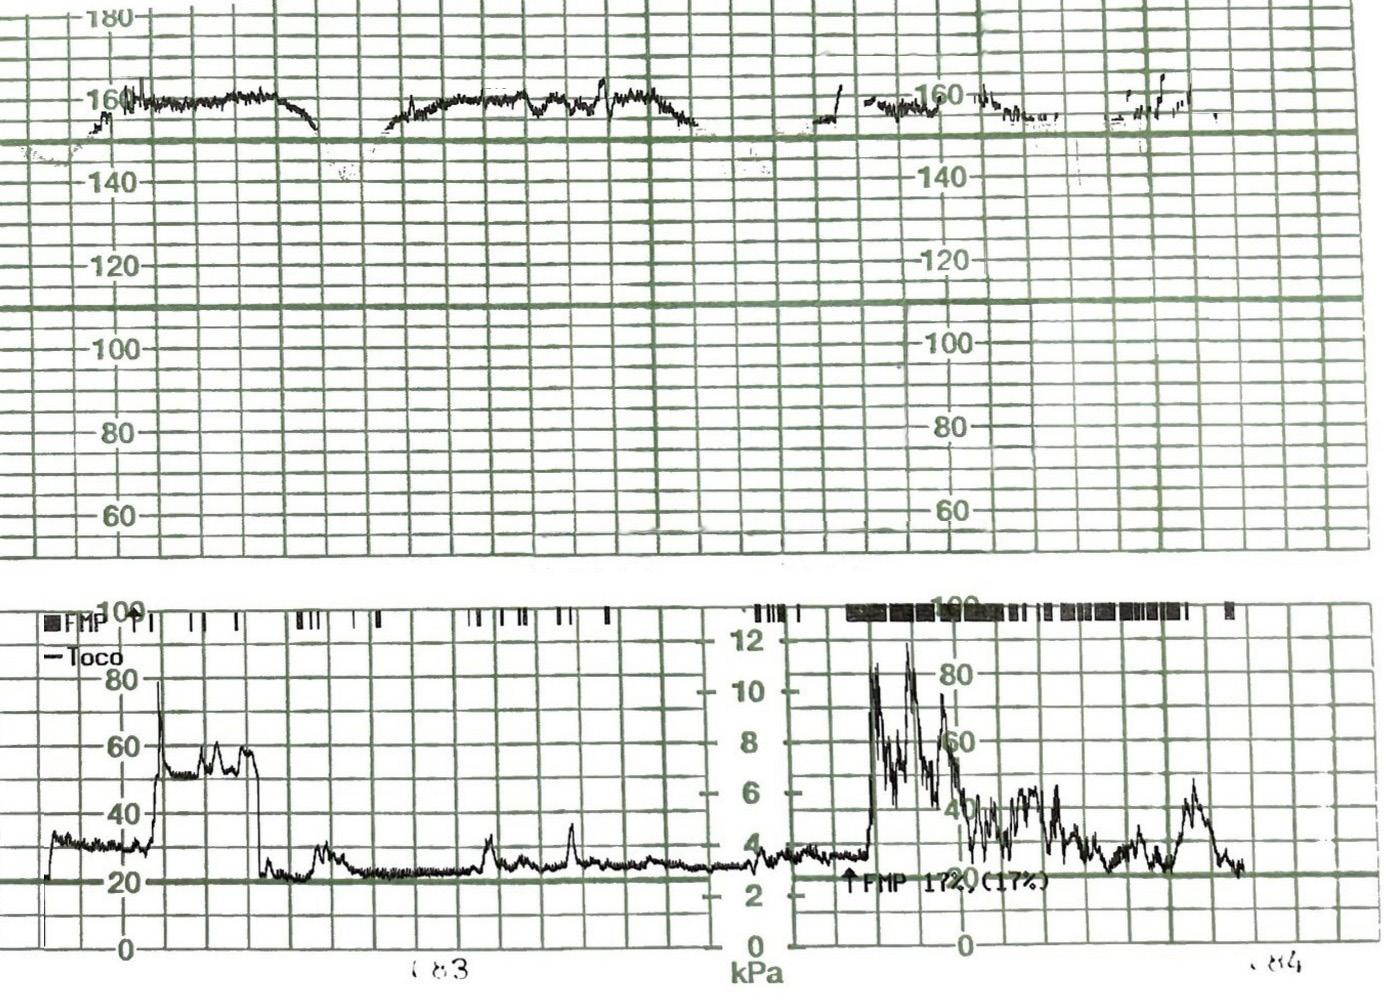

A. Miros, A. Paśnikowska, M. Romanowska, Zespół Barnarda jako rzadka przyczyna niedrożności jelita cienkiego... 53

ści o opisywanej etiologii, zwłaszcza gdy chorym jest osoba w wieku podeszłym. Postawienie szybkiego rozpoznania bywa utrudnione ze względu na często współwystępujący z wiekiem zespół otępienny, który uniemożliwia zebranie wywiadu. Istotną rolę w diagnostyce odgrywają badania RTG oraz TK. Istnieje wiele możliwości terapeutycznych, jednak zawsze należy spośród nich wybrać tę najbardziej optymalną i bezpieczną dla pacjenta, nie siląc się na jednoczasowe, duże operacje odtwórcze. W sytuacjach takich jak opisana ryzyko powikłań związanych z wykonaniem obciążającej i rozległej operacji może przeważać nad przewidywaną korzyścią z zabiegu.

Piśmiennictwo

1. Halabi W.J., Kang C.Y., Ketana N. et al.: Surgery for gallstone ileus: a nationwide comparison of trends and outcomes. Ann Surg 2014; 259(2): 329-335.

2. Tsang C.F.: A rare case of gallstone ileus – the unanswered question. J Surg Case Rep 2021; 2021(4): rjab164.

3. Lourenço S., Pereira A.M., Reis J. et al.: Gallstone ileus: an improbable cause of mechanical small bowel obstruction. Cureus 2020; 12(11): e11460.